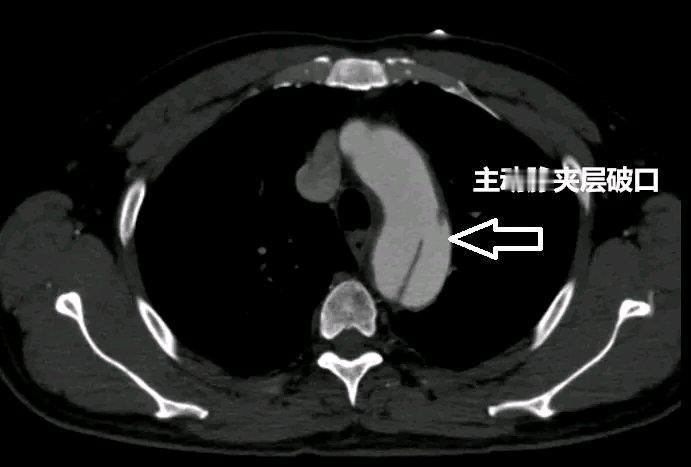

夫妻因孩子教育问题起争执,丈夫情绪激动致血管撕裂近40厘米 参与救治医生讲述 事发突然:争执引发的惊险状况 参与救治的医生回忆,当天丈夫被紧急送来时,情况十分危急。他面色苍白,冷汗直冒,双手捂着胸口,呼吸急促且痛苦不堪。经检查发现,其血管撕裂近40厘米,这在临床上是极为严重的情况,血管壁就像被撕开了一条大口子,血液随时可能大量涌出,危及生命。 全力救治:与死神赛跑 医生们迅速组成了抢救小组,争分夺秒地制定治疗方案。手术台上,每一个动作都精准而迅速,大家全神贯注,不敢有丝毫懈怠。因为血管撕裂的位置特殊且创口大,手术难度极高,稍有不慎就可能导致患者大出血。经过数小时的紧张奋战,终于成功修复了撕裂的血管,将丈夫从死神手中拉了回来。 事后反思:情绪管理与家庭沟通 医生感慨,因家庭琐事情绪激动引发如此严重的后果实在令人惋惜。在日常生活中,夫妻间因孩子教育问题产生分歧很常见,但一定要学会控制情绪,采用平和有效的沟通方式。这次事件给这对夫妻,也给所有家庭敲响了警钟,情绪管理和良好的沟通在家庭生活中至关重要。